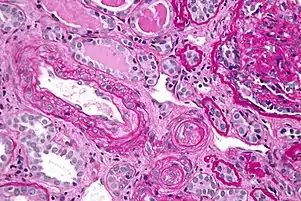

| Micrograph of thrombotic microangiopathy with the characteristic onion-skin layering seen in older lesions. PAS stain. | |